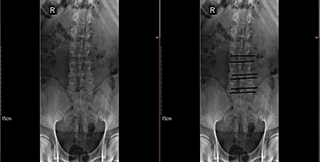

Se solicitó una radiografía AP de columna lumbar con datos de espondiloartrosis degenerativa y disminución del espacio L5-S1.